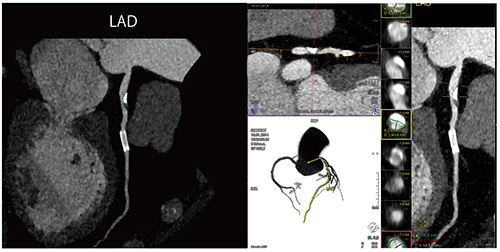

心臓CTにおいても,選択可能なあらゆる技術において最適な線量を用いることが重要である(Right Dose Imaging)(図5)。また,SOMATOM Forceでは,第三世代の逐次近似画像再構成法である“ADMIRE(Advanced Modeled Iterative Reconstruction)”により,さらなる画質の向上が可能である。Case4は,ステント内腔評価のため受診した症例である。分解能の向上に加え,ステント内のブルーミングアーチファクトが低減されており,ステント内狭窄を適切に診断できる(図6)。また,非石灰化プラークも,きわめて良好に描出されている。

図6 Case4:69歳,ステント内腔狭窄疑い(造影剤量40mL,DLP 250mGy・cm)